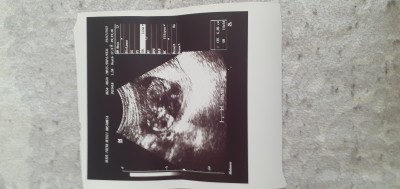

29 Temmuz 2022 Hamilelik Dönemi Genel kategorisinde (79 puan) sordu

hanımlar merhaba bugün doktora gttm ama doktor cinsiyet daha erken dedi merk edyrm anlayan yorum yapablrmi teşekkürler simdiden

Gebelik haftası 13+2

Çok uzak çekim hiç birşey belli olmuyor